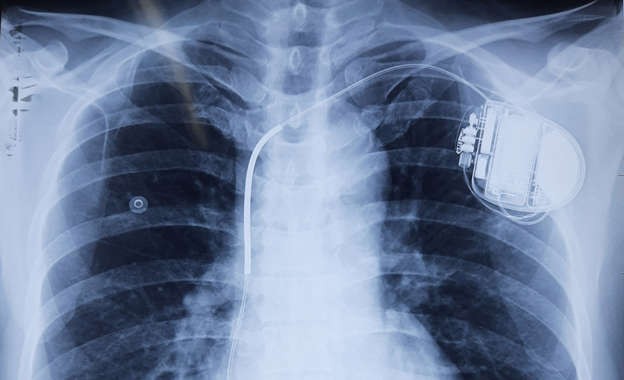

Bệnh nhân trên trước đây từng ngất hai lần, may mắn qua khỏi. Để dự phòng những cơn loạn nhịp tim khác có thể cướp đi sinh mạng bệnh nhân, các bác sĩ chỉ định cấy máy phá rung tự động (ICD). Bác sĩ Liêm cho hay đây là một phương pháp hiệu quả và an toàn trong y học hiện đại giúp dự phòng đột tử do các rối loạn nhịp tim nguy hiểm.

Theo đó, máy ICD được cấy ghép dưới xương đòn bệnh nhân, một dây điện cực kết nối từ máy vào buồng tim phải qua đường tĩnh mạch dưới đòn. Máy sẽ ghi nhận và theo dõi tất cả mọi hoạt động điện học của tim. Khi tim xuất hiện tình trạng rối loạn nhịp, tín hiệu bất thường này sẽ chuyển tới máy ICD, máy phát dòng điện để cắt những cơn rối loạn, đưa trái tim trở về nhịp co bóp bình thường, ngăn ngừa nguy cơ đột tử.